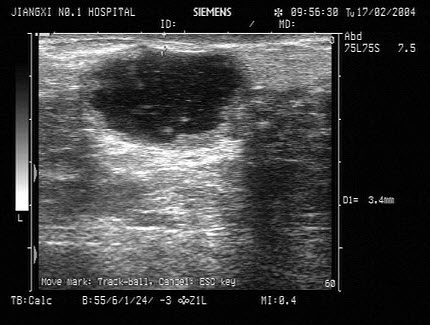

59、单项选择题

某患者,既往有肾炎病史。因头晕,无尿三日入院,根据其肝右叶-右肾声像图,最可能的诊断为()

A.慢性肾衰

B.急性肾炎

C.肾结核

D.尿路结石

E.慢性肾炎